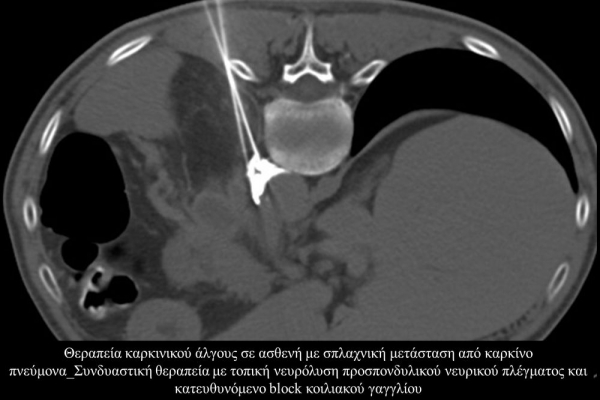

Η αντιμετώπιση του καρκινικού πόνου, εκτός από την κλασική συντηρητική φαρμακευτική θεραπεία, όταν ο πόνος επιμένει ή όταν οι παρενέργειες των φαρμακευτικών μεθόδων εξαντλούν τον ασθενή, περιλαμβάνει ελάχιστα παρεμβατικές τεχνικές με τις οποίες επιτυγχάνεται διακοπή ή καταστροφή της νευρικής οδού μεταβίβασης του πόνου. Η επεμβατική ακτινολογία διαθέτει μια πληθώρα θεραπευτικών τεχνικών που σκοπό έχουν να προσφέρουν ποιοτική βελτίωση της ζωής και των σχέσεων, τόσο των ογκολογικών ασθενών, όσο και των οικογενειών τους.